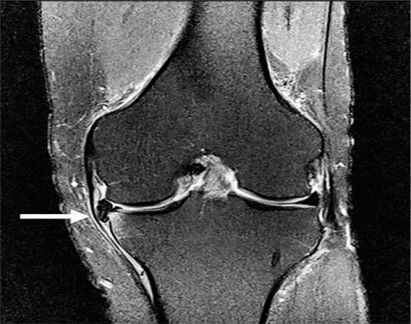

Hình 4. Rách sụn chêm, nang sụn chêm. Hình ảnh coronal xóa mỡ có u nang nhỏ (mũi tên đen) tiếp giáp với thân của sụn chêm bên có vết rách liên quan đến sụn chêm (mũi tên trắng)

Hình 5. Vết rách ngang sụn với mảnh di lệch. Hình ảnh pd xóa mỡ với vết rách sụn chêm giữa và mảnh di lệch (mũi tên) nằm giữa dây chằng chéo giữa và mâm chày giữa.